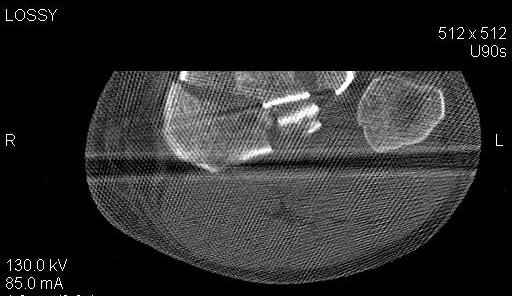

Пациенту сделали КТ - ухитрились сделать на шине Белера (не давал положить прямую ногу) - срезали передний отдел. Планируется на пятницу (24.12) на операцию - синтез длинной мыщелковой LCP-пластиной Synthes :). Отек ближе к слову умеренный (окружность голени +4 см по сравнению со здоровой). КТ и снимок на вытяжении прилагаются.